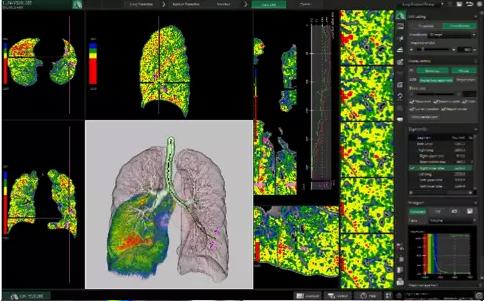

了解更多